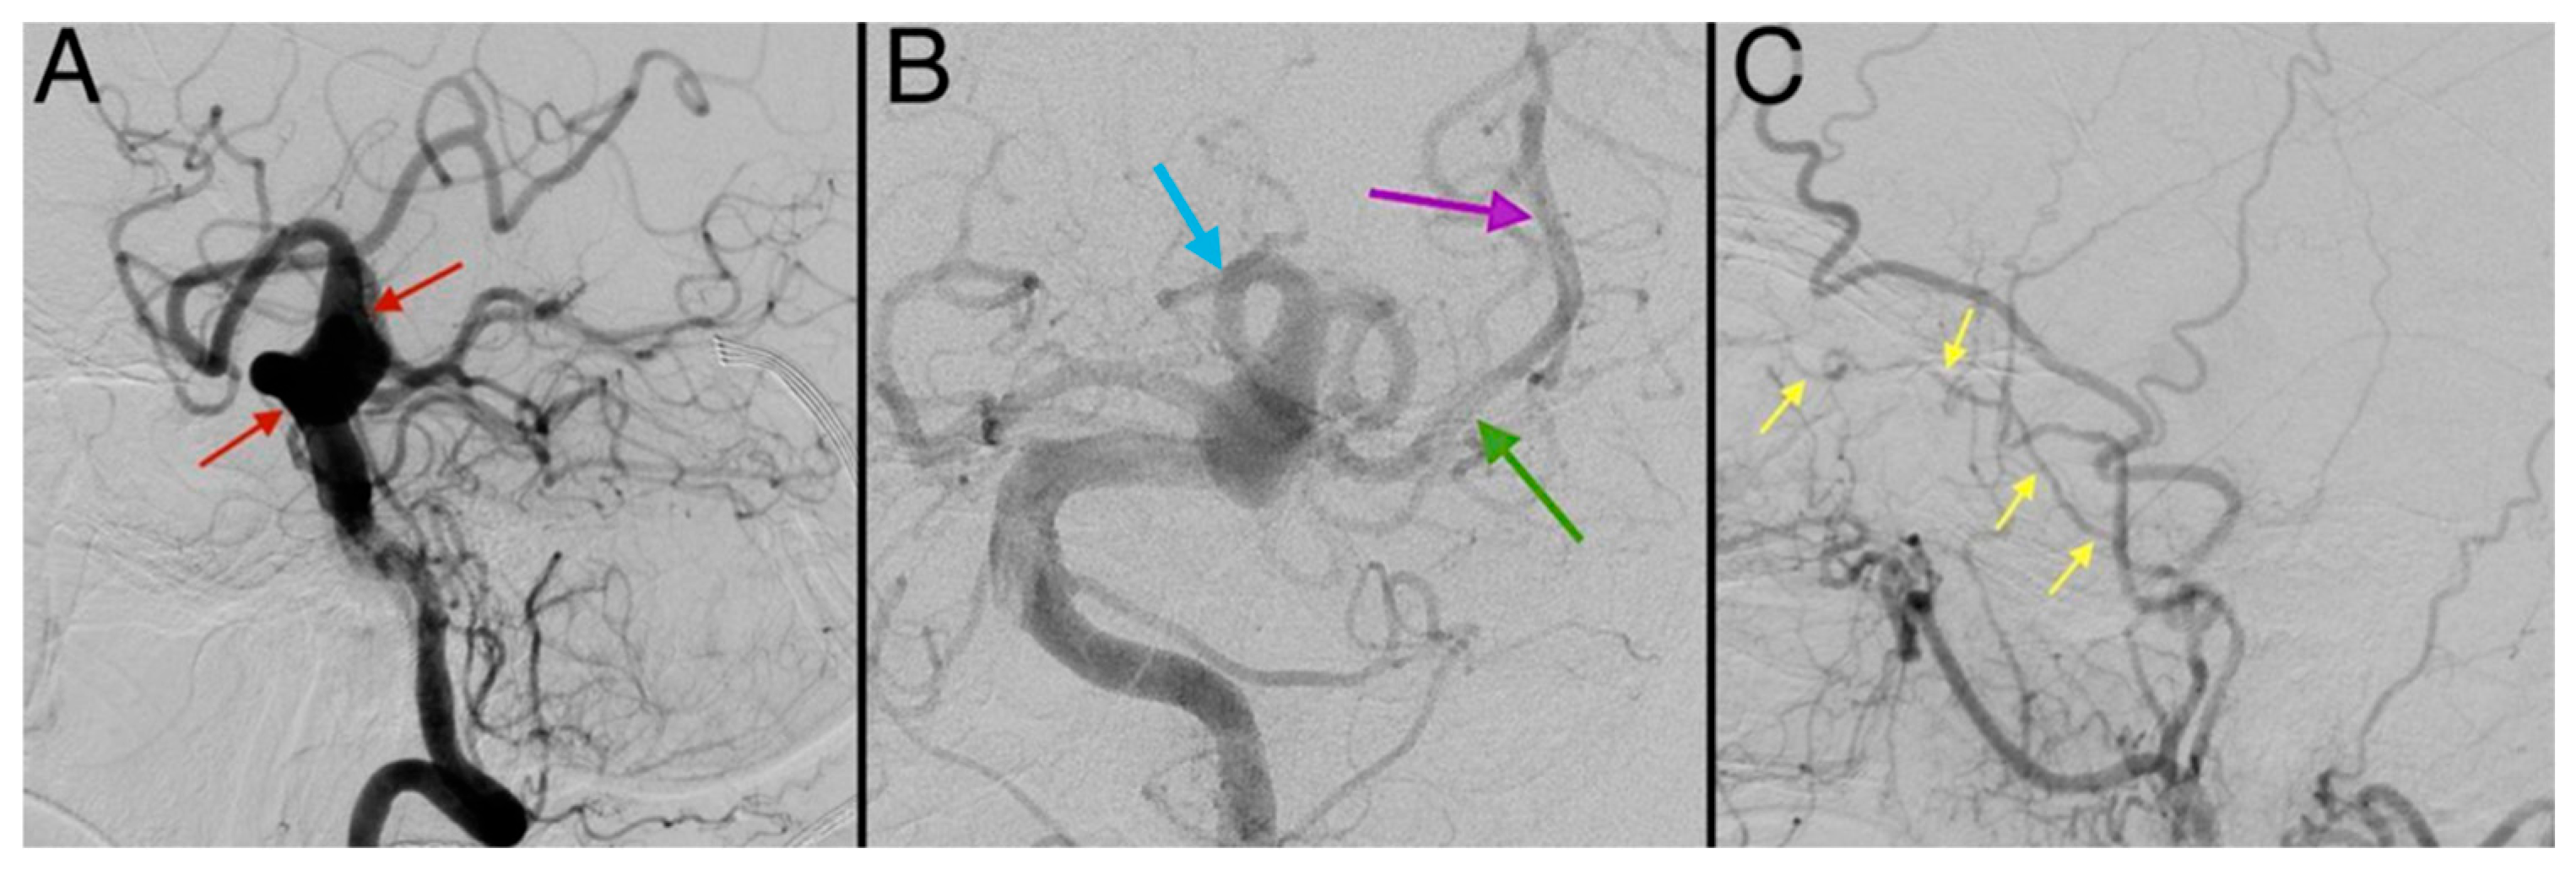

2. Case Report